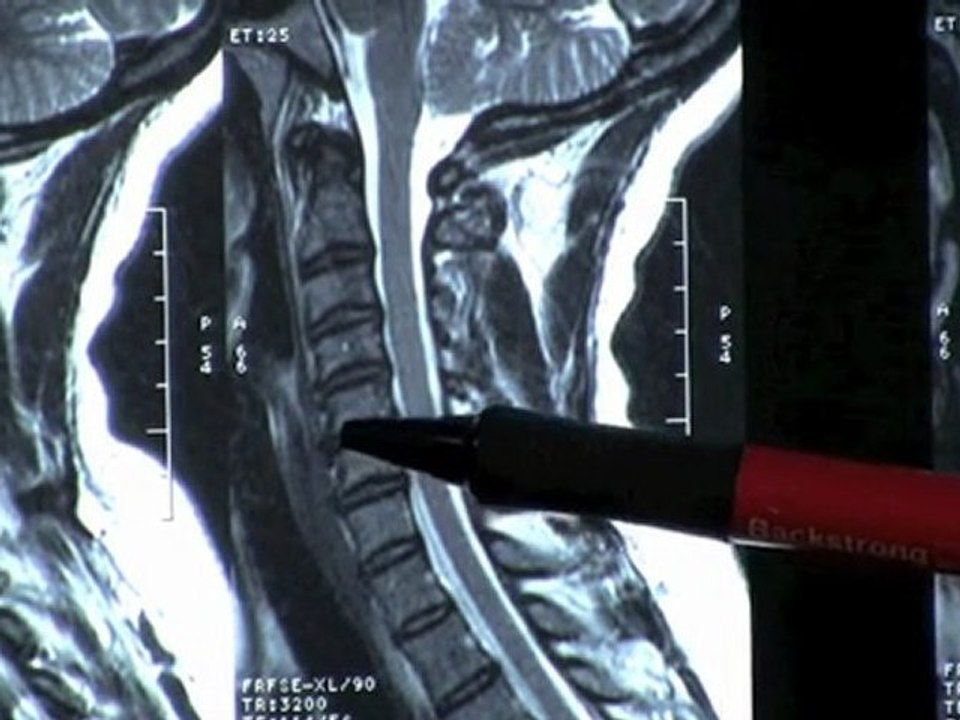

http://www.triangledisc.com. - Eva suffered with sciatic leg pain for months as a result of a bulging disc. She "absolutely" recommends Spinal Decompression Therapy at Triangle Disc Care. <br /><br />Triangle Disc Care <br />2413 Blue Ridge Rd <br />Raleigh, NC 27607 <br />(919) 571-2515 <br /><br />http://www.triangledisc.com/decompression.php <br />http://www.triangledisc.com/backpain.php <br />http://youtu.be/_hkZxqUnjgg